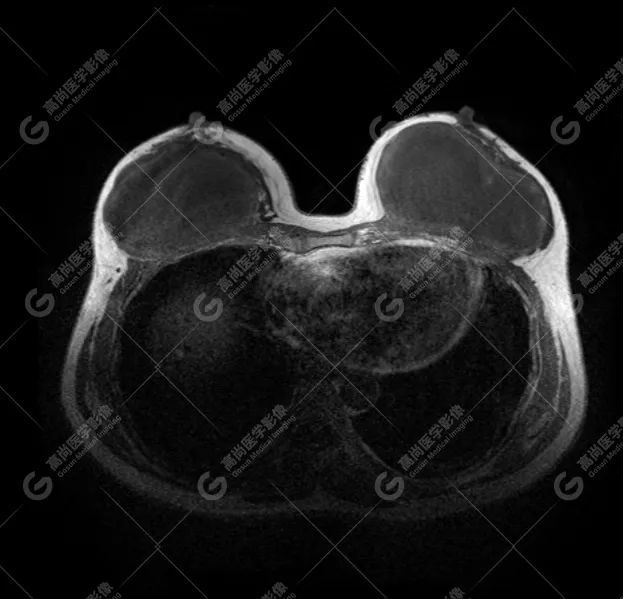

病例 2:乳腺假体植入术后约 1 年

双侧假体内包膜可见多发皱褶影,提示包膜趋向挛缩。